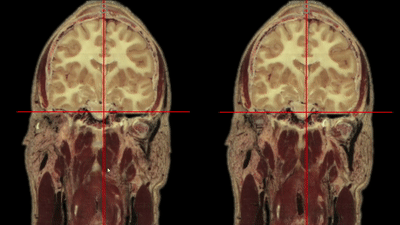

nv.get_volume_data ( x1, x2, y1, y2, z1, z2 )

maybe?

endless processing possibilities :)

nv.set_volume_data ( x1, x2, y1, y2, z1, z2, new data )

nv.set_label_data ( x1, x2, y1, y2, z1, z2, new data )

nv.get_label_data ( x1, x2, y1, y2, z1, z2 )

Goal: Nobrainer models as Boostlet!

Satra Ghosh's Senseable Intelligence Group

ROI Selection

Shruti Varade

all different!

soon in Boostlet.js!